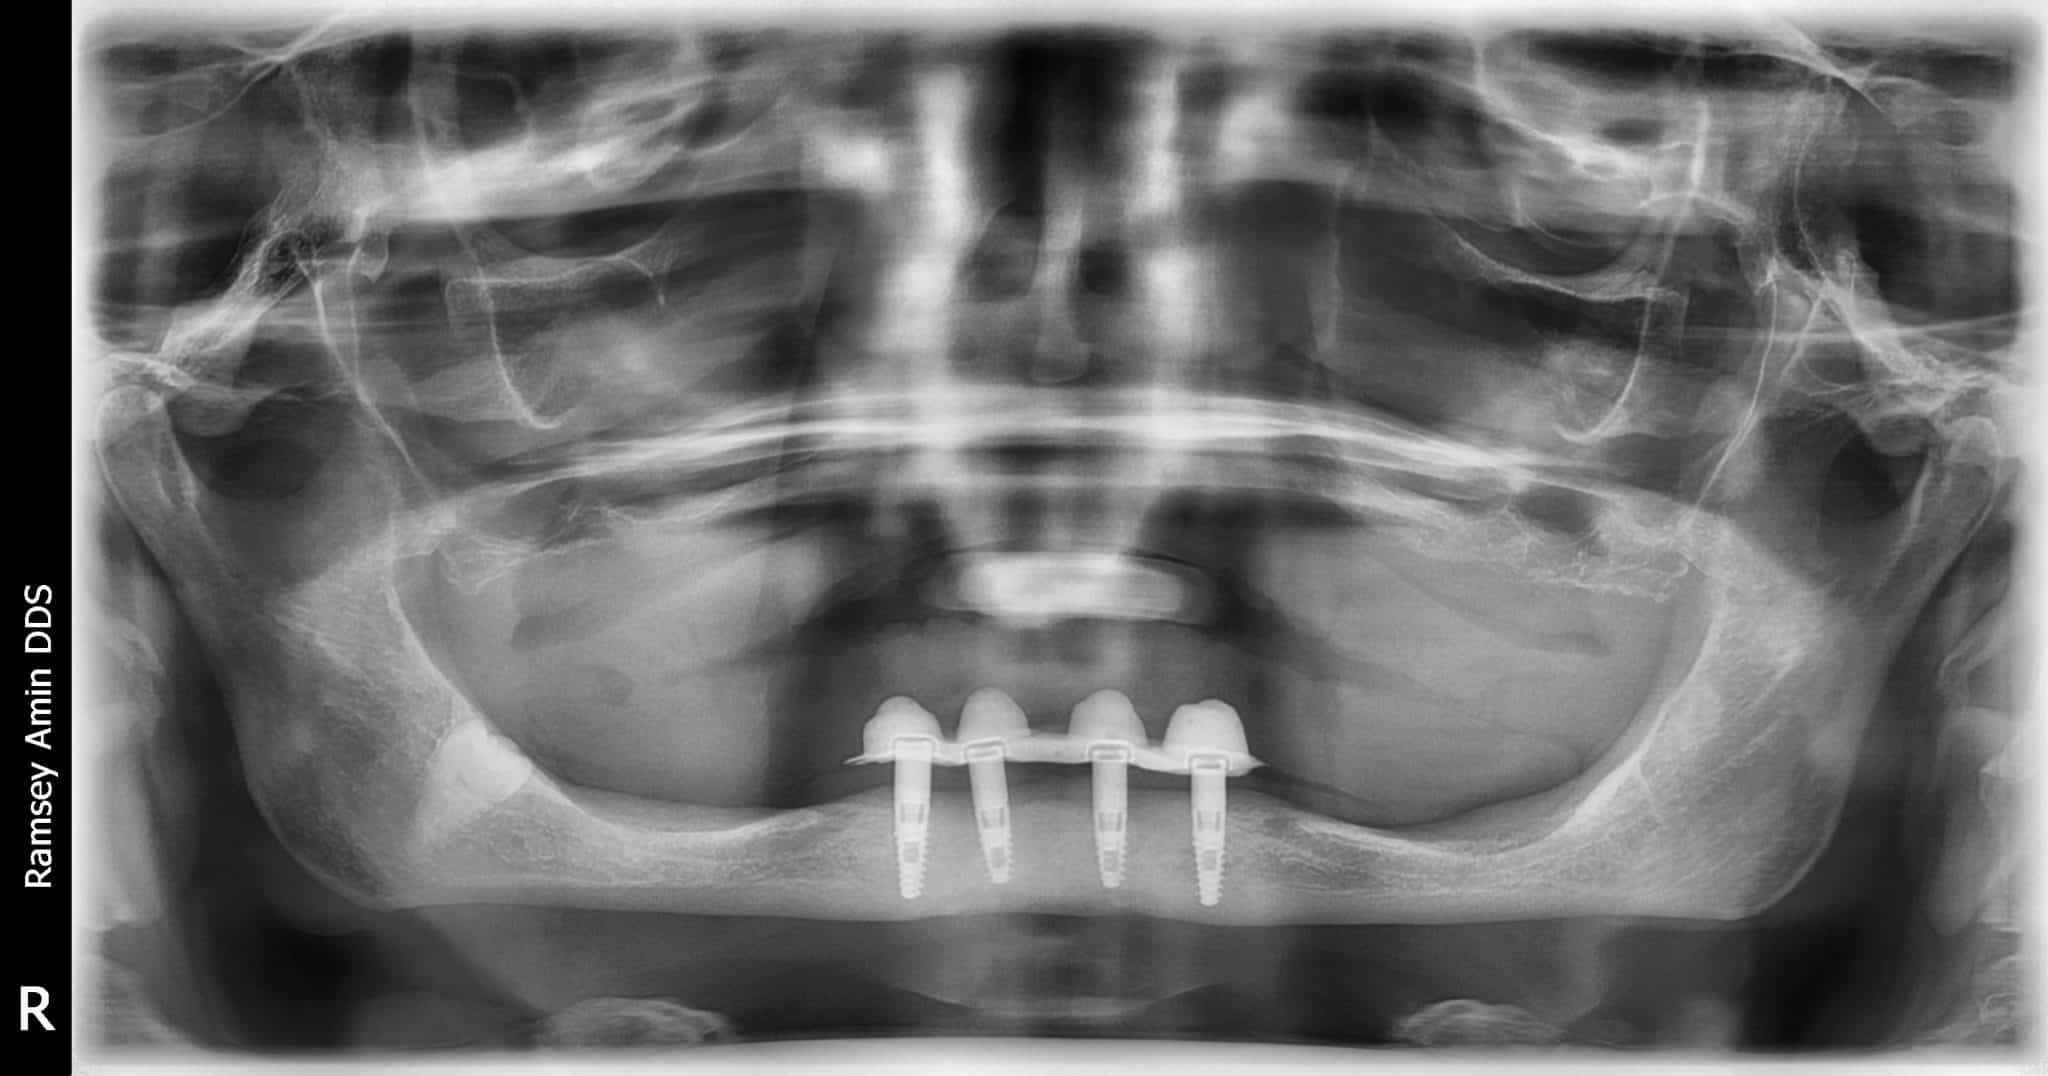

ComplicationsBone Graft For Failed Full Lower Dental Implants Ramsey A. Amin, DDS Tooth Extraction And Bone Graft Complications Scott froum discusses tooth extraction prevalence in the us and offers a decision matrix to clarify when. dental bone graft side effects and complications include infection or abscess, nerve damage, and sinus problems. learn why and how to get a bone graft after tooth extraction to prevent bone loss and prepare for dental implants. learn when and. Tooth Extraction And Bone Graft Complications.

ComplicationsBone Graft For Failed Full Lower Dental Implants Tooth Extraction And Bone Graft Complications learn why and how to get a bone graft after tooth extraction to prevent bone loss and prepare for dental implants. Find out the types, benefits, cost, recovery time, and tips for this procedure. a dental bone graft is a procedure to increase bone in the jaw for implants, tooth loss, or gum disease. The bone graft procedure. Tooth Extraction And Bone Graft Complications.

ComplicationsBone Graft For Failed Full Lower Dental Implants Tooth Extraction And Bone Graft Complications a dental bone graft is a procedure to increase bone in the jaw for implants, tooth loss, or gum disease. Find out the types, benefits, cost, recovery time, and tips for this procedure. learn why and how to get a bone graft after tooth extraction to prevent bone loss and prepare for dental implants. learn when and. Tooth Extraction And Bone Graft Complications.